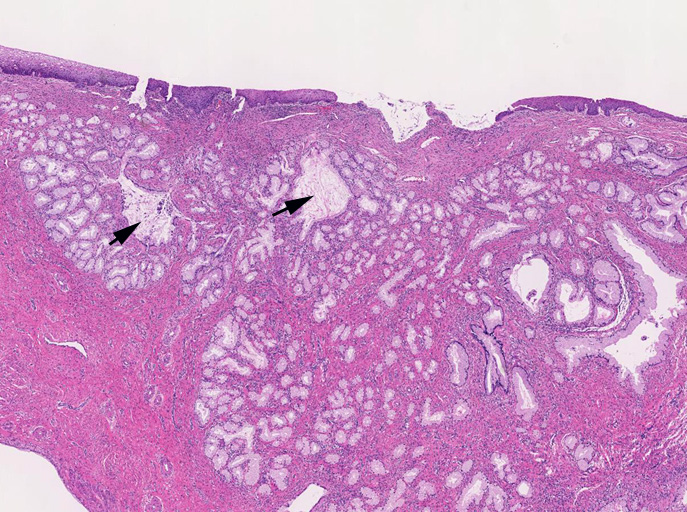

子宮頚管腺に類似した高円柱上皮よりなる腺管の著明な増生を認める。これらは大型で拡張した導管様腺管と,それを囲繞するように配列する分葉状構造をしめす小型腺管からなり, 嚢胞状に拡張した腺管も随所に認められる。最深部にみられる腺上皮は, 嚢胞状に拡張した腺管の一部と考えられる。

loupe像では, 拡張した導管を中心に高円柱上皮からなる腺管が分葉状に配置する所見が認められる。